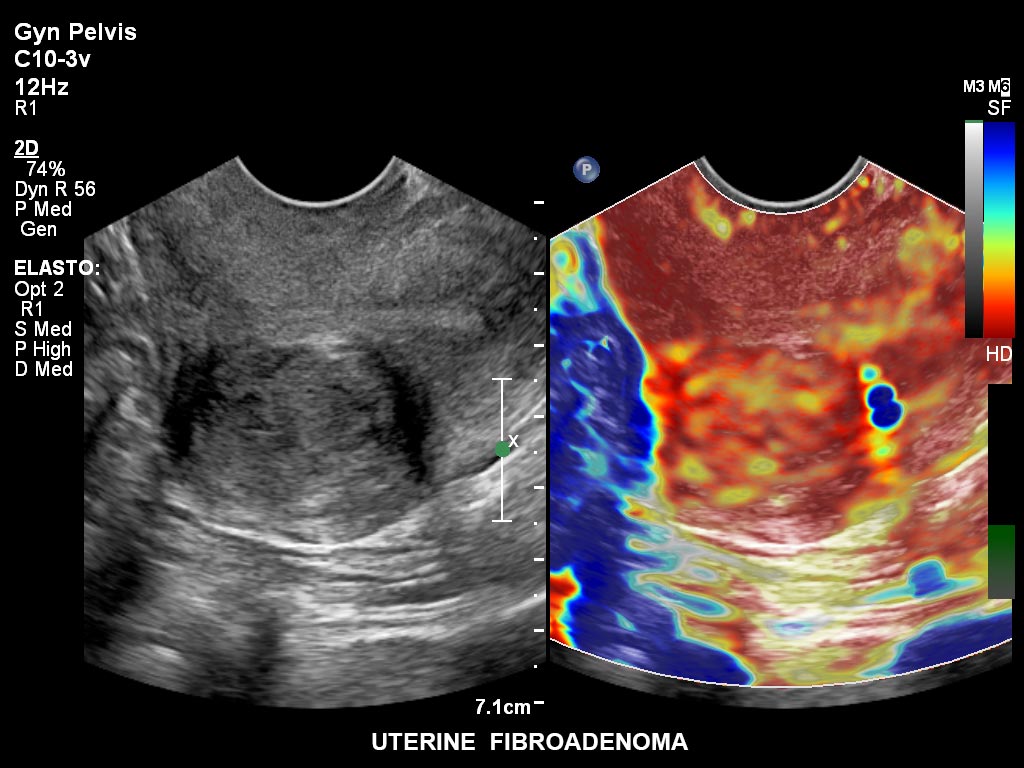

Die EPIQ-Produktreihe mit ausgereiften Schallköpfen erfüllt die Anforderungen auch Ihrer anspruchsvollsten gynäkologischen Untersuchungen und während der gesamten Schwangerschaft.

• C10-3v PureWave-Breitband-Endo-Convex-Schallkopf, ideal für anspruchsvolle Myom- und komplexe Ovar-Untersuchungen sowie Bildgebung im ersten Schwangerschaftstrimester